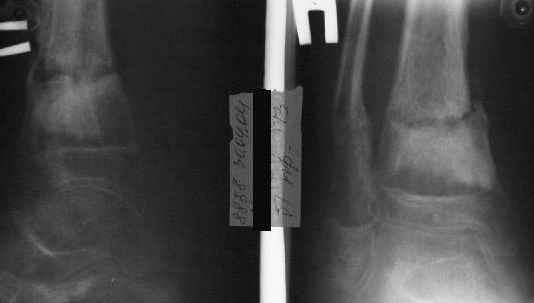

В январе 2005: варусная деформация н\3 голени, болевой с-м, комбинированная контрактура г\стопного сустава, нейропатия м\берцового нерва сохраняется слабость разгибания 1 пальца.

Операции: 1 Клиновидная резекция на вершине деформации м\берцовой кости.

2 Тугоподвижный ложный сустав н\3 б\берцовой кости. Рубцы выполняющие пространство между отломками, канал проксимального отломка иссечены.

Одномоментное устранение деформации, остеосинтез Г-образной пластиной.

Пластика по Хахутову.

Заживление проксимальной части раны вторичным натяжением без нагноения. Рана зажила. Спицы удалены через 1,5 недели после операции.

Учитывая фон (интеллект, etc) гипсовая повязка.

На данный момент ходит при помощи костыля (без присмотра -без костыля :), разрабатывает движения в г\стопном суставе.